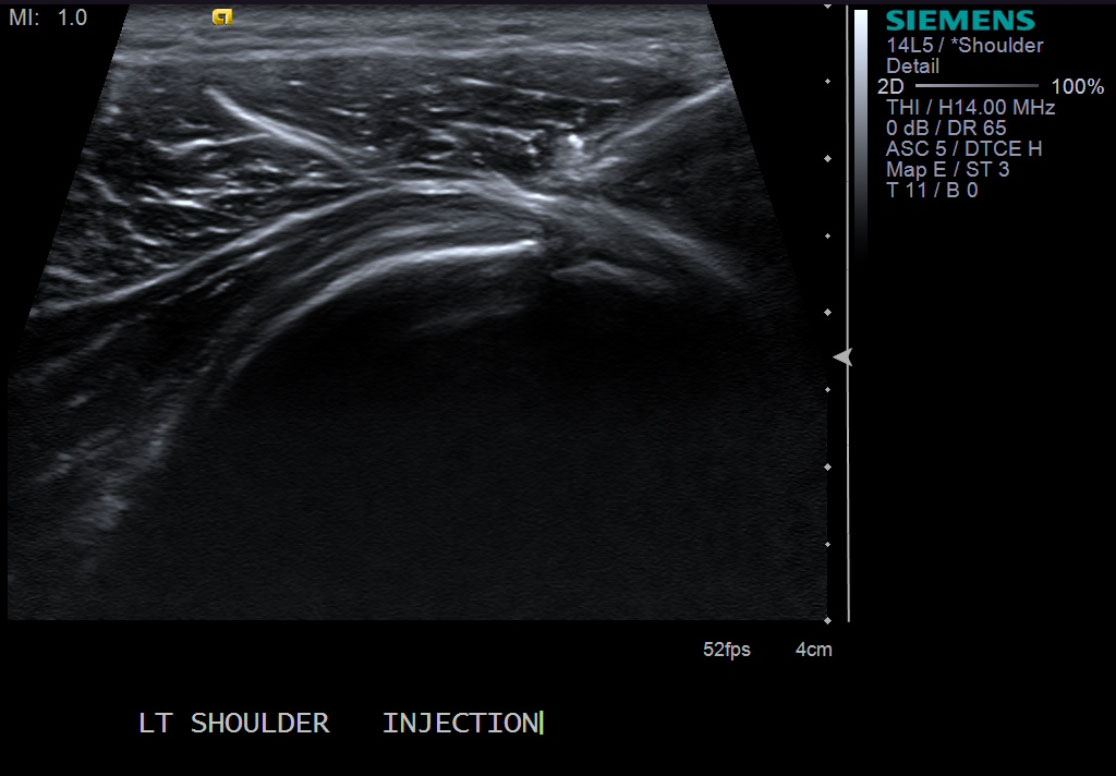

• descriptiondescription

• Needle has been advanced and is about to broach the infraspinatus tendon. If one were to do a test injection at this point, there would be resistance to flow.